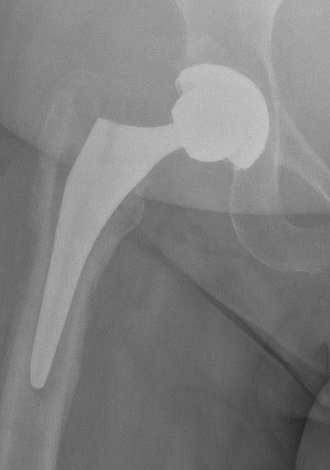

X-ray

1. Progressive radiolucent lines / rapid lysis

2. Focal osteolysis with endosteal scalloping

3. Periosteal new bone

- pathognomonic of infection

- usually at junction meta / diaphysis on medial side

- uncommon

Femoral stem lysis Acetabular lysis